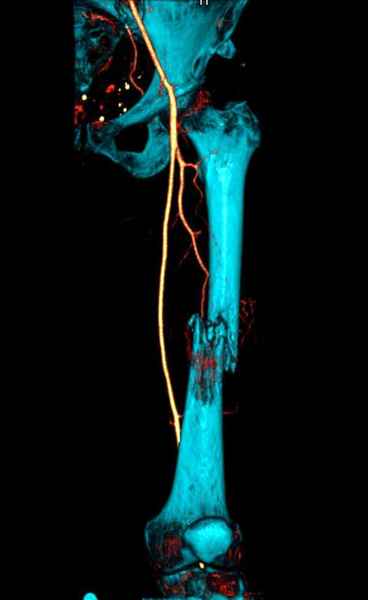

Для предупреждения кровотечения во время рассверливания, за день до операции провели эмболизацию сосудов питающий метастаз. http://radiology.rsnajnls.org/cgi/reprint/150/3/673.pdf (7-11, 12-15-16)

С минимальным рассверливанием и ретроградным методом провели остеосинтез бедра 12 мм гвоздем. (17-20)